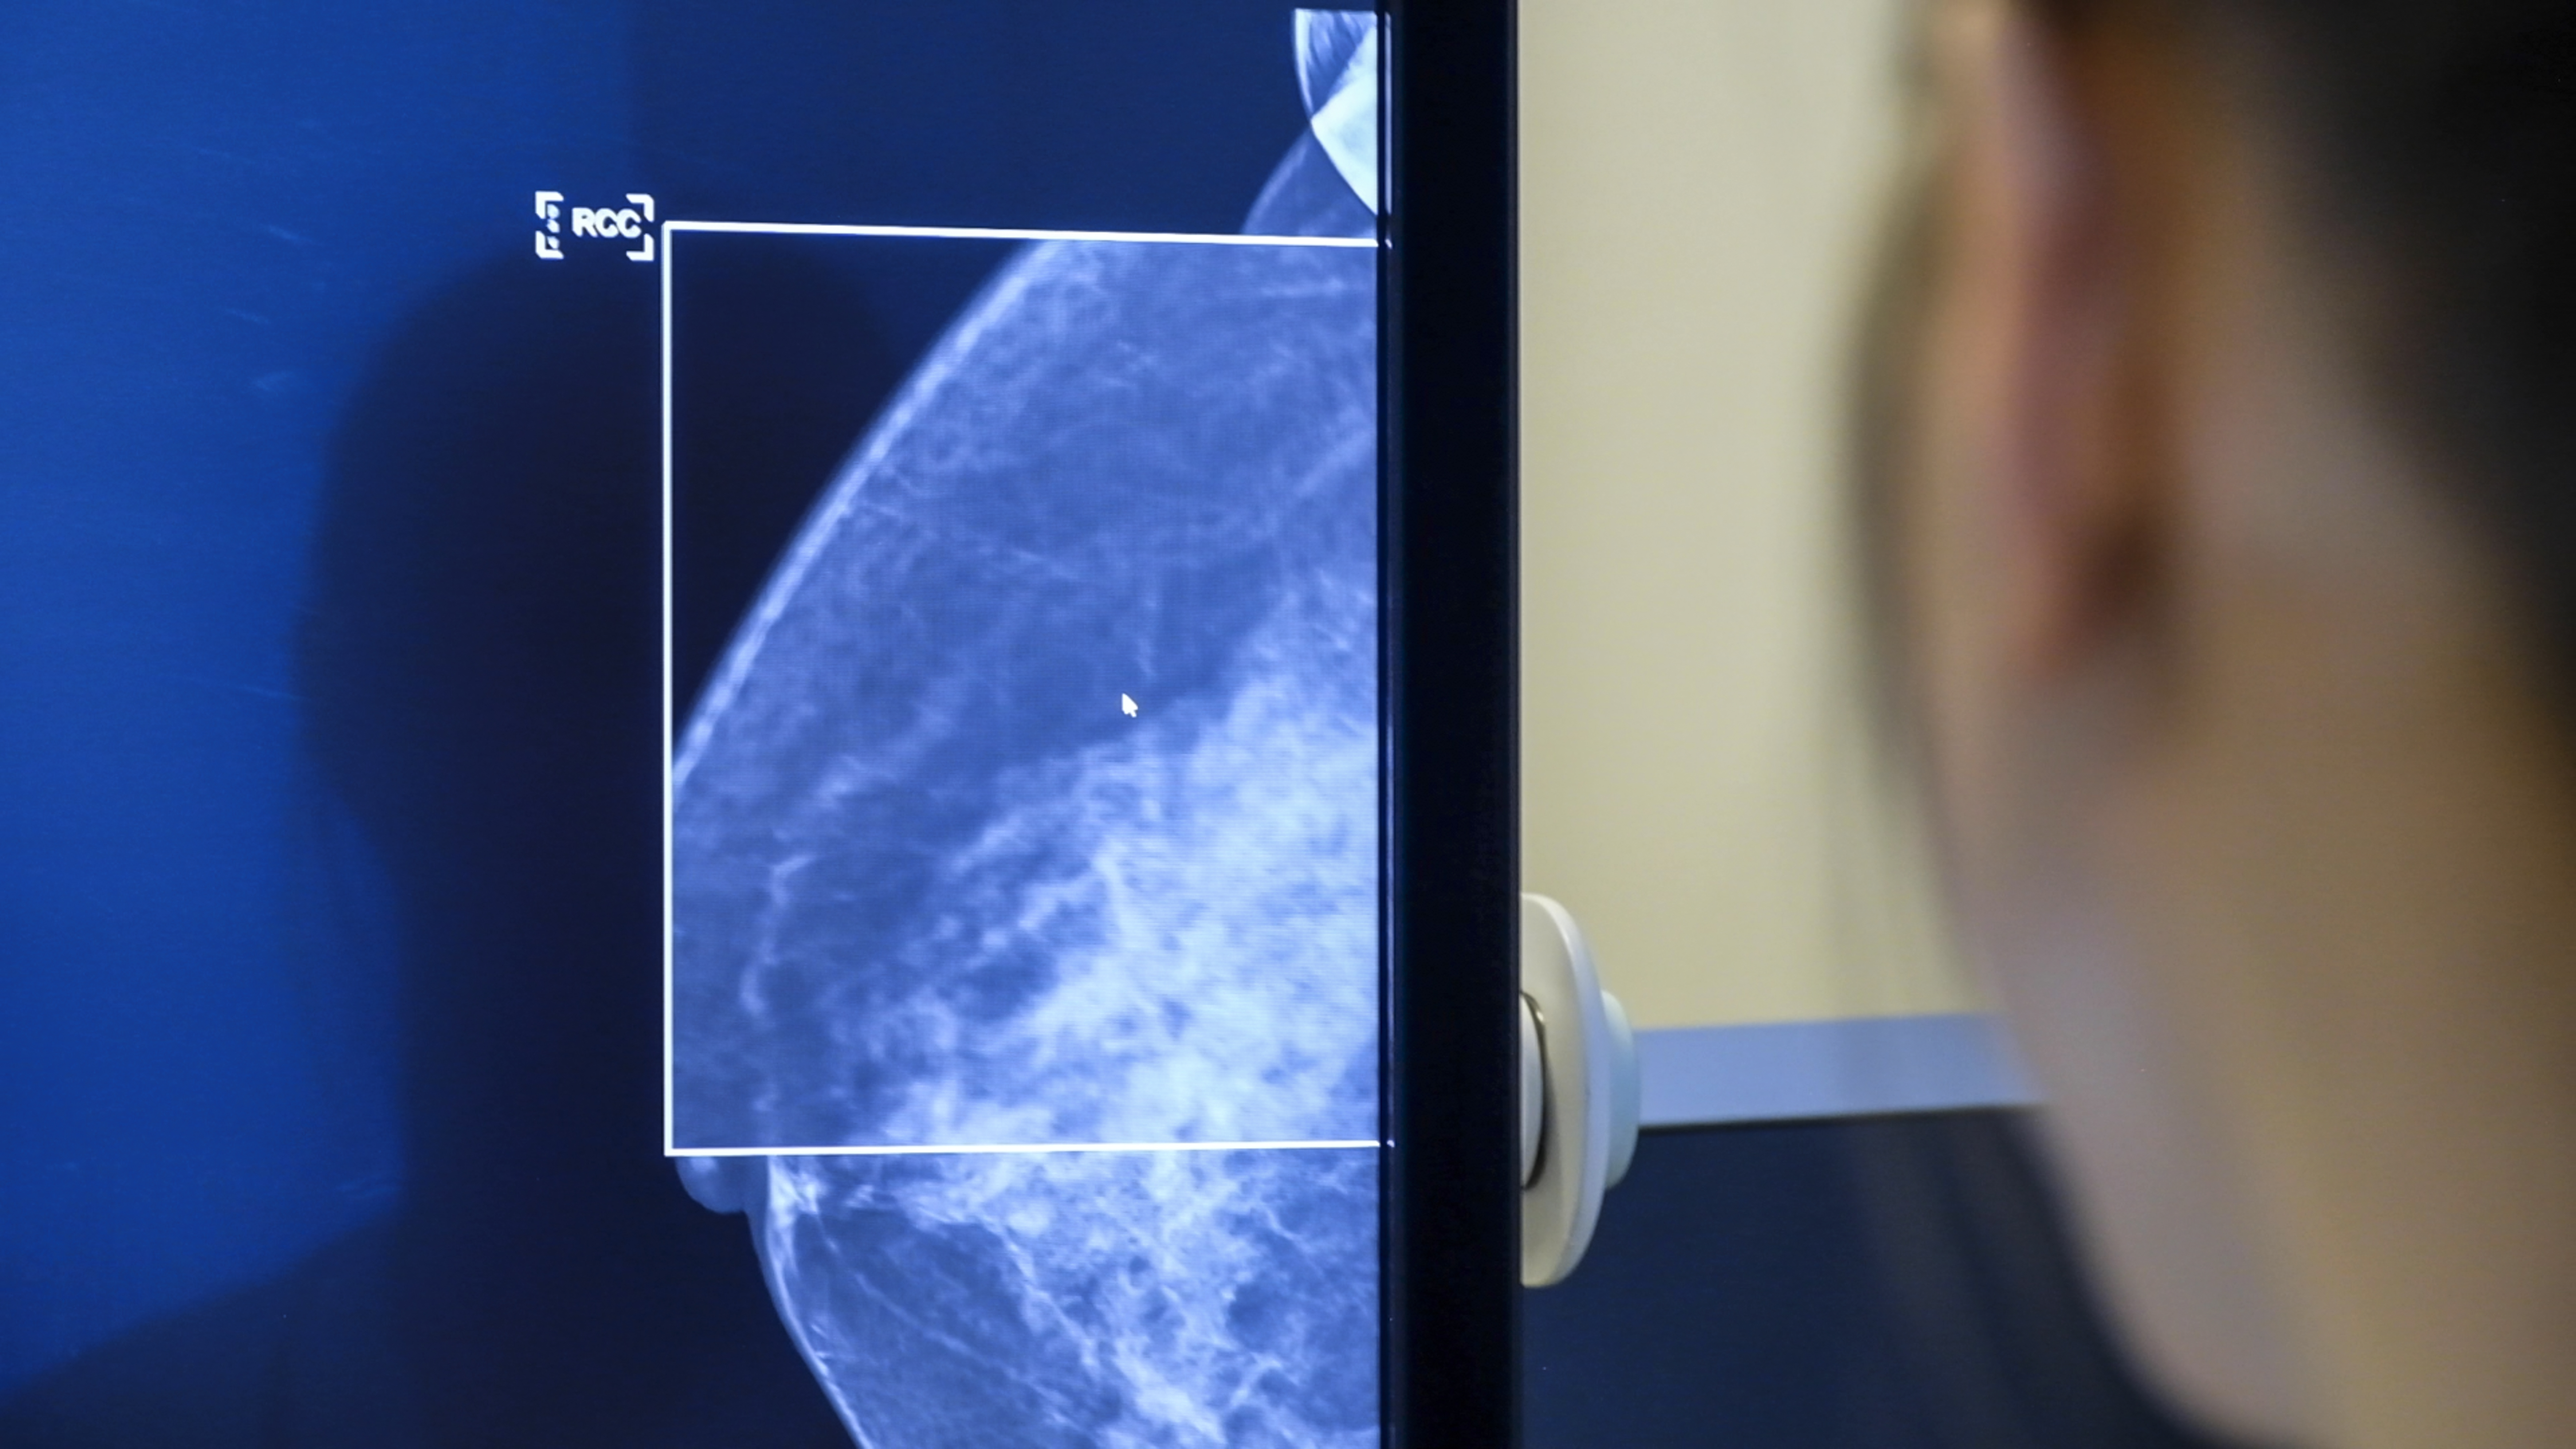

I Sverige kallas alla kvinnor mellan 40-74 år till regelbunden screening med hjälp av mammografi, för att upptäcka bröstcancer. Genom mammografi kan man hitta en bröstcancer i ett tidigt skede och därmed öka chansen för lindrigare behandling och överlevnad. Ungefär 2 av 3 bröstcancerfall upptäcks på det sättet.

En fjärdedel av all bröstcancer hittas dock hos kvinnor över 74 år, det vill säga hos kvinnor som redan är urfasade ur screeningprogrammen. Konsekvensen av det är att dubbelt så många cancerfall då upptäcks i ett senare skede av sjukdomen, jämfört med hos de kvinnor som fortfarande omfattas av screeningprogrammet. Cancerfonden vill nu se en modernisering av screeningprogrammet och att Socialstyrelsen ser över möjligheten till en riskanpassad screening efter 74 år. Något som idag skulle kunna vara möjligt tack vare ny teknik.

— Det som har hänt nu är otroligt spännande, att man bara genom att AI analyserar själva mammografibilden bättre kan förutsäga risk än med de klassiska kliniska modellerna. Det vore ett enkelt sätt börja individualisera screeningen utifrån den enskilda kvinnans risk, säger Sophia Zachrisson.